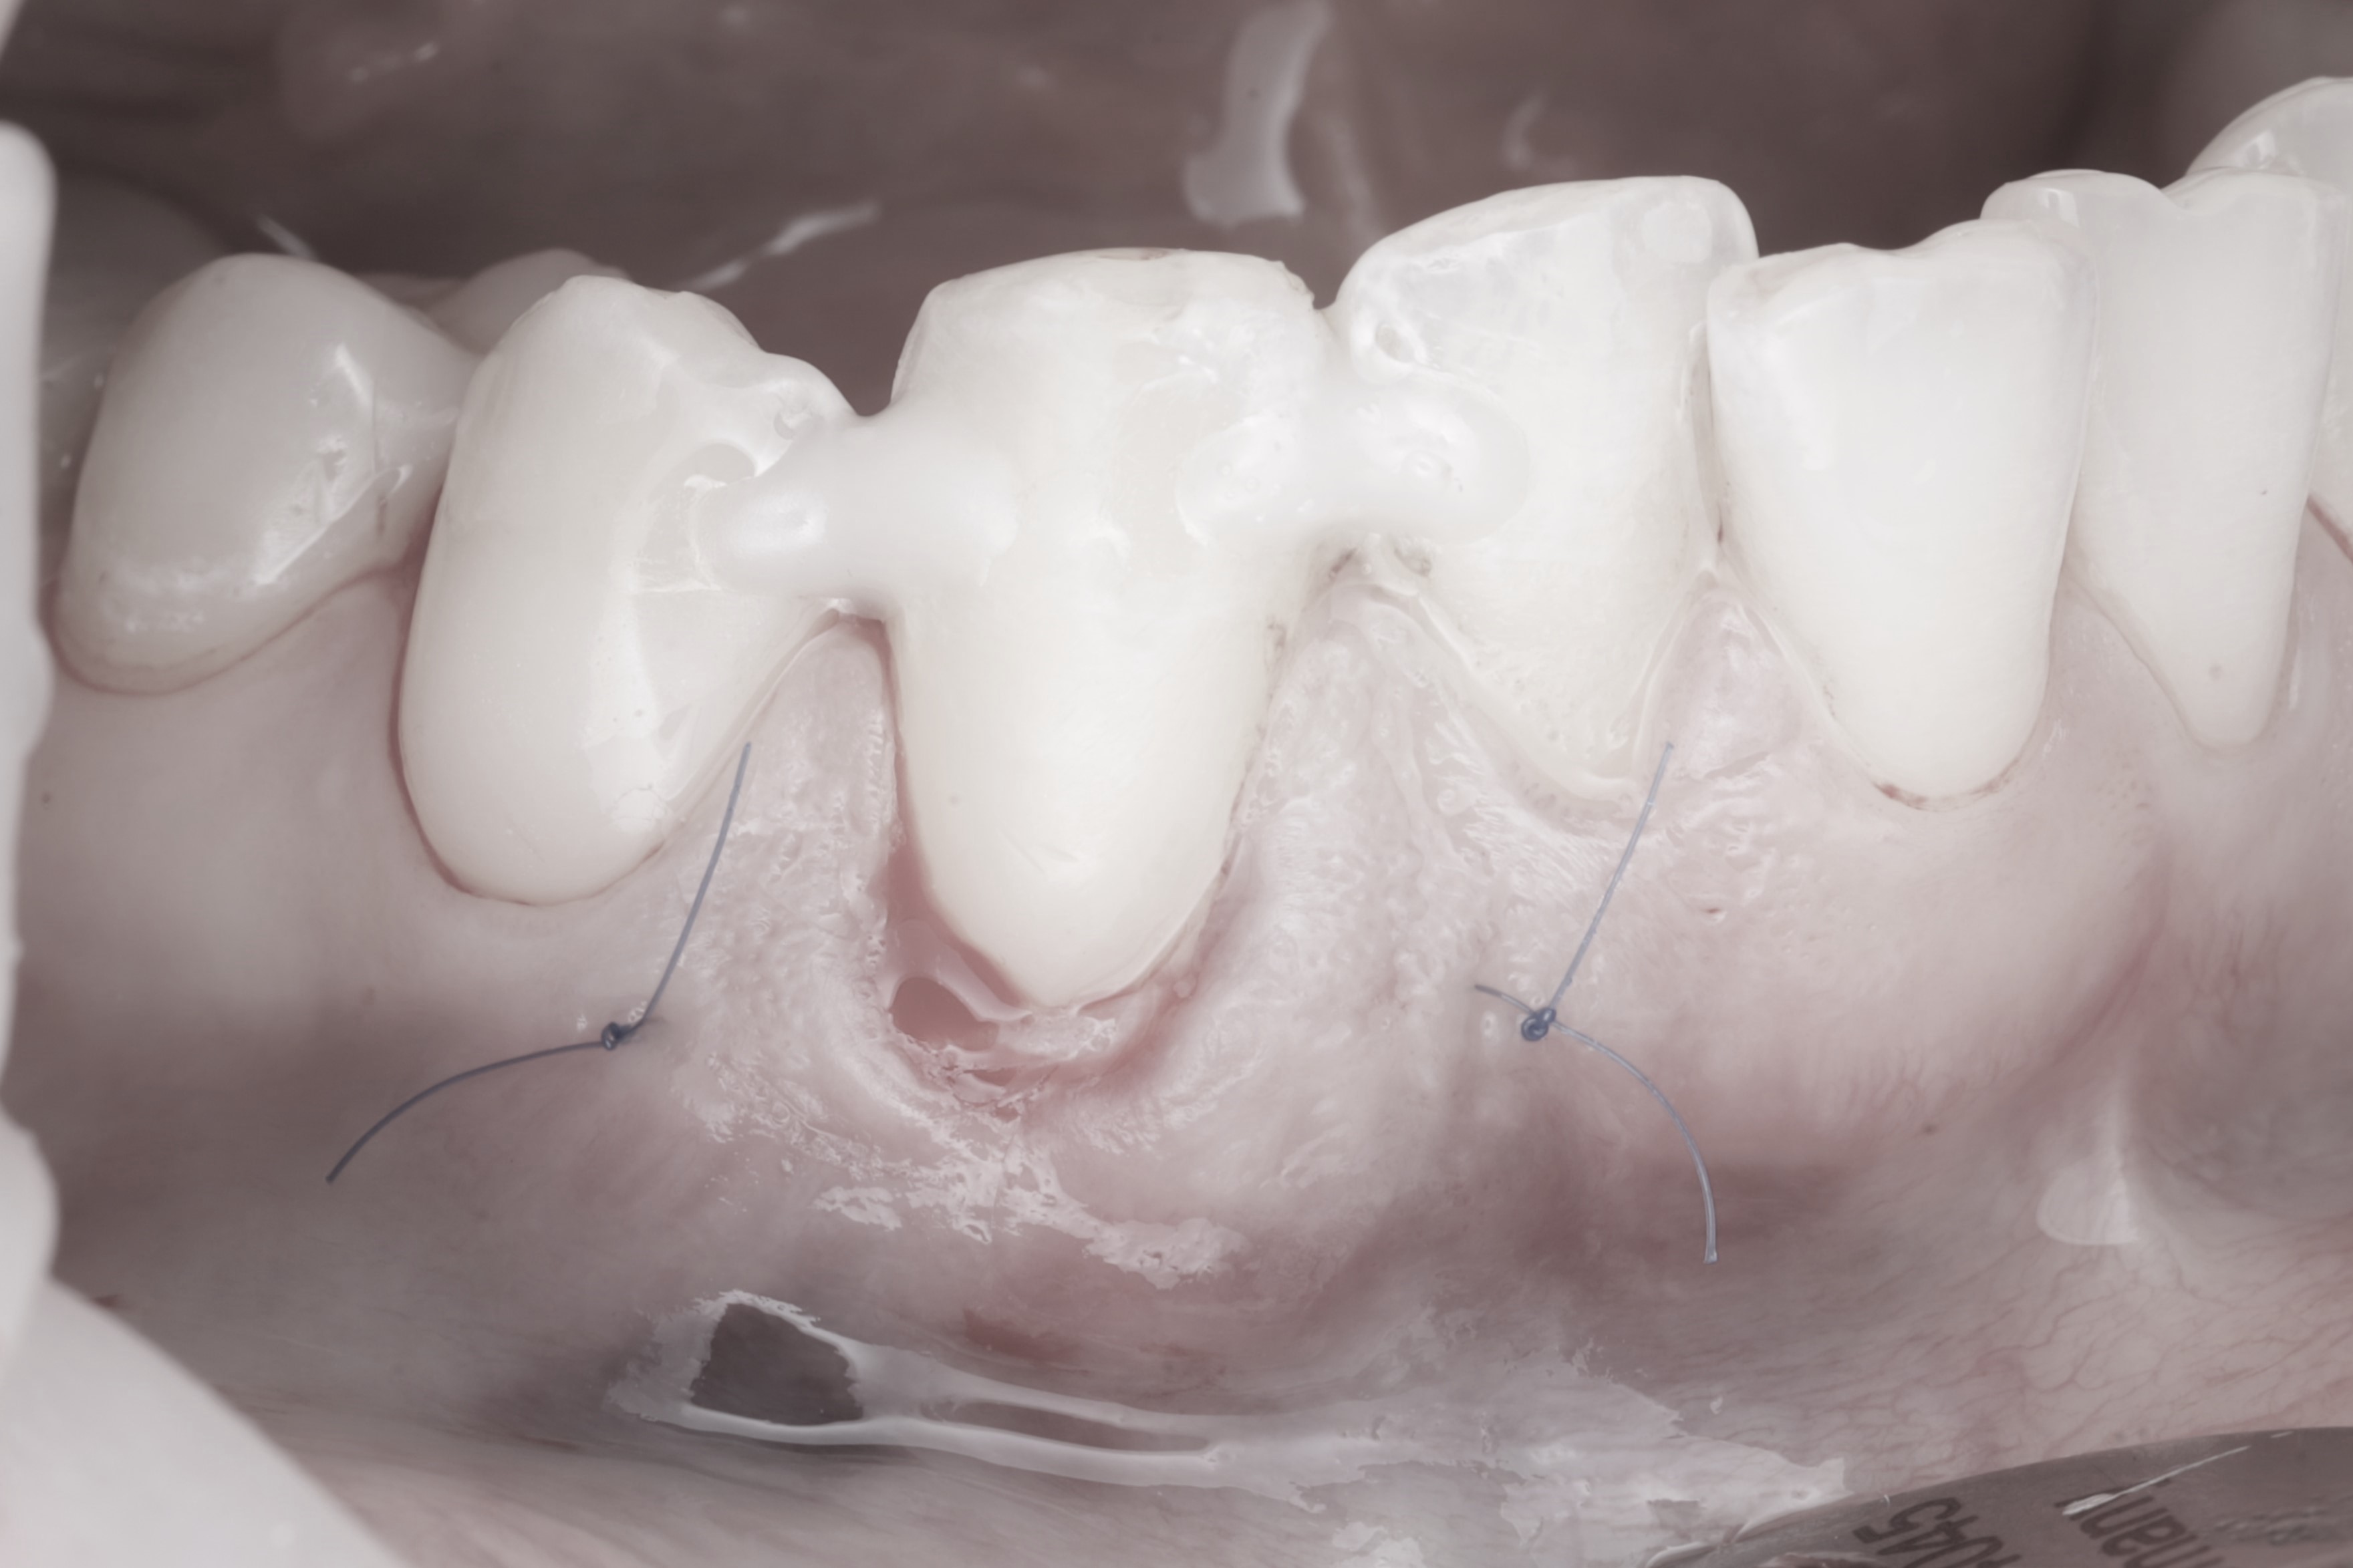

Спустя месяц пациентка с уже санированной полостью рта была направлена на закрытие рецессий. Терапевт произвёл закрытие рецессий десны композитным материалом. Также было запланировано пришлифовывание материала в полости рта и закрытие небольшой рецессии на зубе 4.4.

Операция была выполнена туннельной техникой с получением десневого трансплантата с нёба